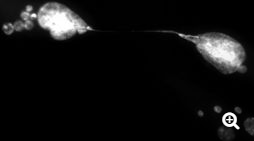

To achieve such results, Rodier’s research team was able to count on state-of-the-art imaging equipment funded by the Institut du cancer de Montréal.

“Genetically, we were able to reproduce the phenomenon of cellular aging in the laboratory and ensured that all the telomeres of a population of cells became dysfunctional,” said PhD student Marc-Alexandre Olivier, co-first author of the study with former colleague Sabrina Ghadaouia, currently pursuing postdoctoral studies in England. “With our equipment, we then observed in real time what was happening inside each single cell.”